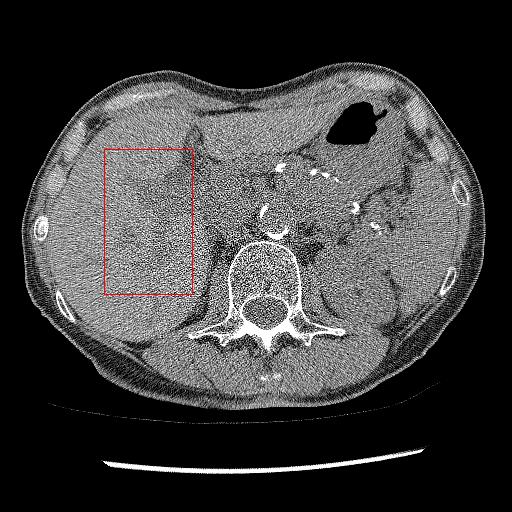

Figure 8: Result of denoising for comparison. We have shown an example of denoising performance on image taken from the ELCAP Public Lung Image Database. The display window is [175175-175, 240] HU. Readers are requested to zoom in for better view.

Figure 9: Comparison of denoising performance of different network. Zoomed view of the region inside the bounding box shown in the images for Figure 8

Here, we analyse the performance of the proposed method on clinical data. Since there are no ground truths available, only qualitative comparisons are performed. An example of the denoising performance of the proposed method is given in Figure 8. Here we can see denoising performance of BM3D is the worst compared to other methods. On the other hand, the output of the deep image prior is very blurry, different organ boundary is distorted, and some splotchy artifacts appear in the image. The performance of DIP depends mainly on the stopping iteration; with more iterations, it will again produce the original noisy image. The clean image produced by it is always blurry and without any texture. Consistent with our previous example, we can see CycleGAN has a lot of residual noise left in the example. Next, we identified one hypodense lesion in the image and marked the region with the red colour bounding box. The zoomed version of the region containing the lesion is shown in Figure 9. The effect of denoising is perceptible in this zoomed view. The visibility of the lesion is very inconspicuous in the original LDCT image. The noise variance is very high in this region; consequently, BM3D and CycleGAN failed to remove noise from this region. On the other hand, DIP has removed the noise but also destroyed the image by removing all the texture information. ConsensusNet also produced a blurry version of the lesion in the output. At the same time, our method produced a denoised image with the lowest granular pattern and improved the lesion’s visibility. The main objective of image denoising is to restore the visibility of these types of lesions and anomalies by concealing the noise. In this regard, our method has reached the goal as the perceptibility of different anomalies has been improved vastly without losing structural or textural information.